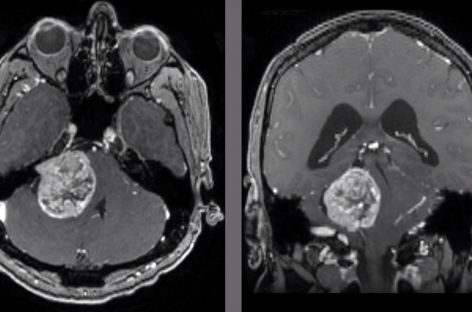

Cercetări de pionierat privind opţiuni de tratament pentru una dintre cele mai agresive forme de cancer cerebralastăzi, 12:02